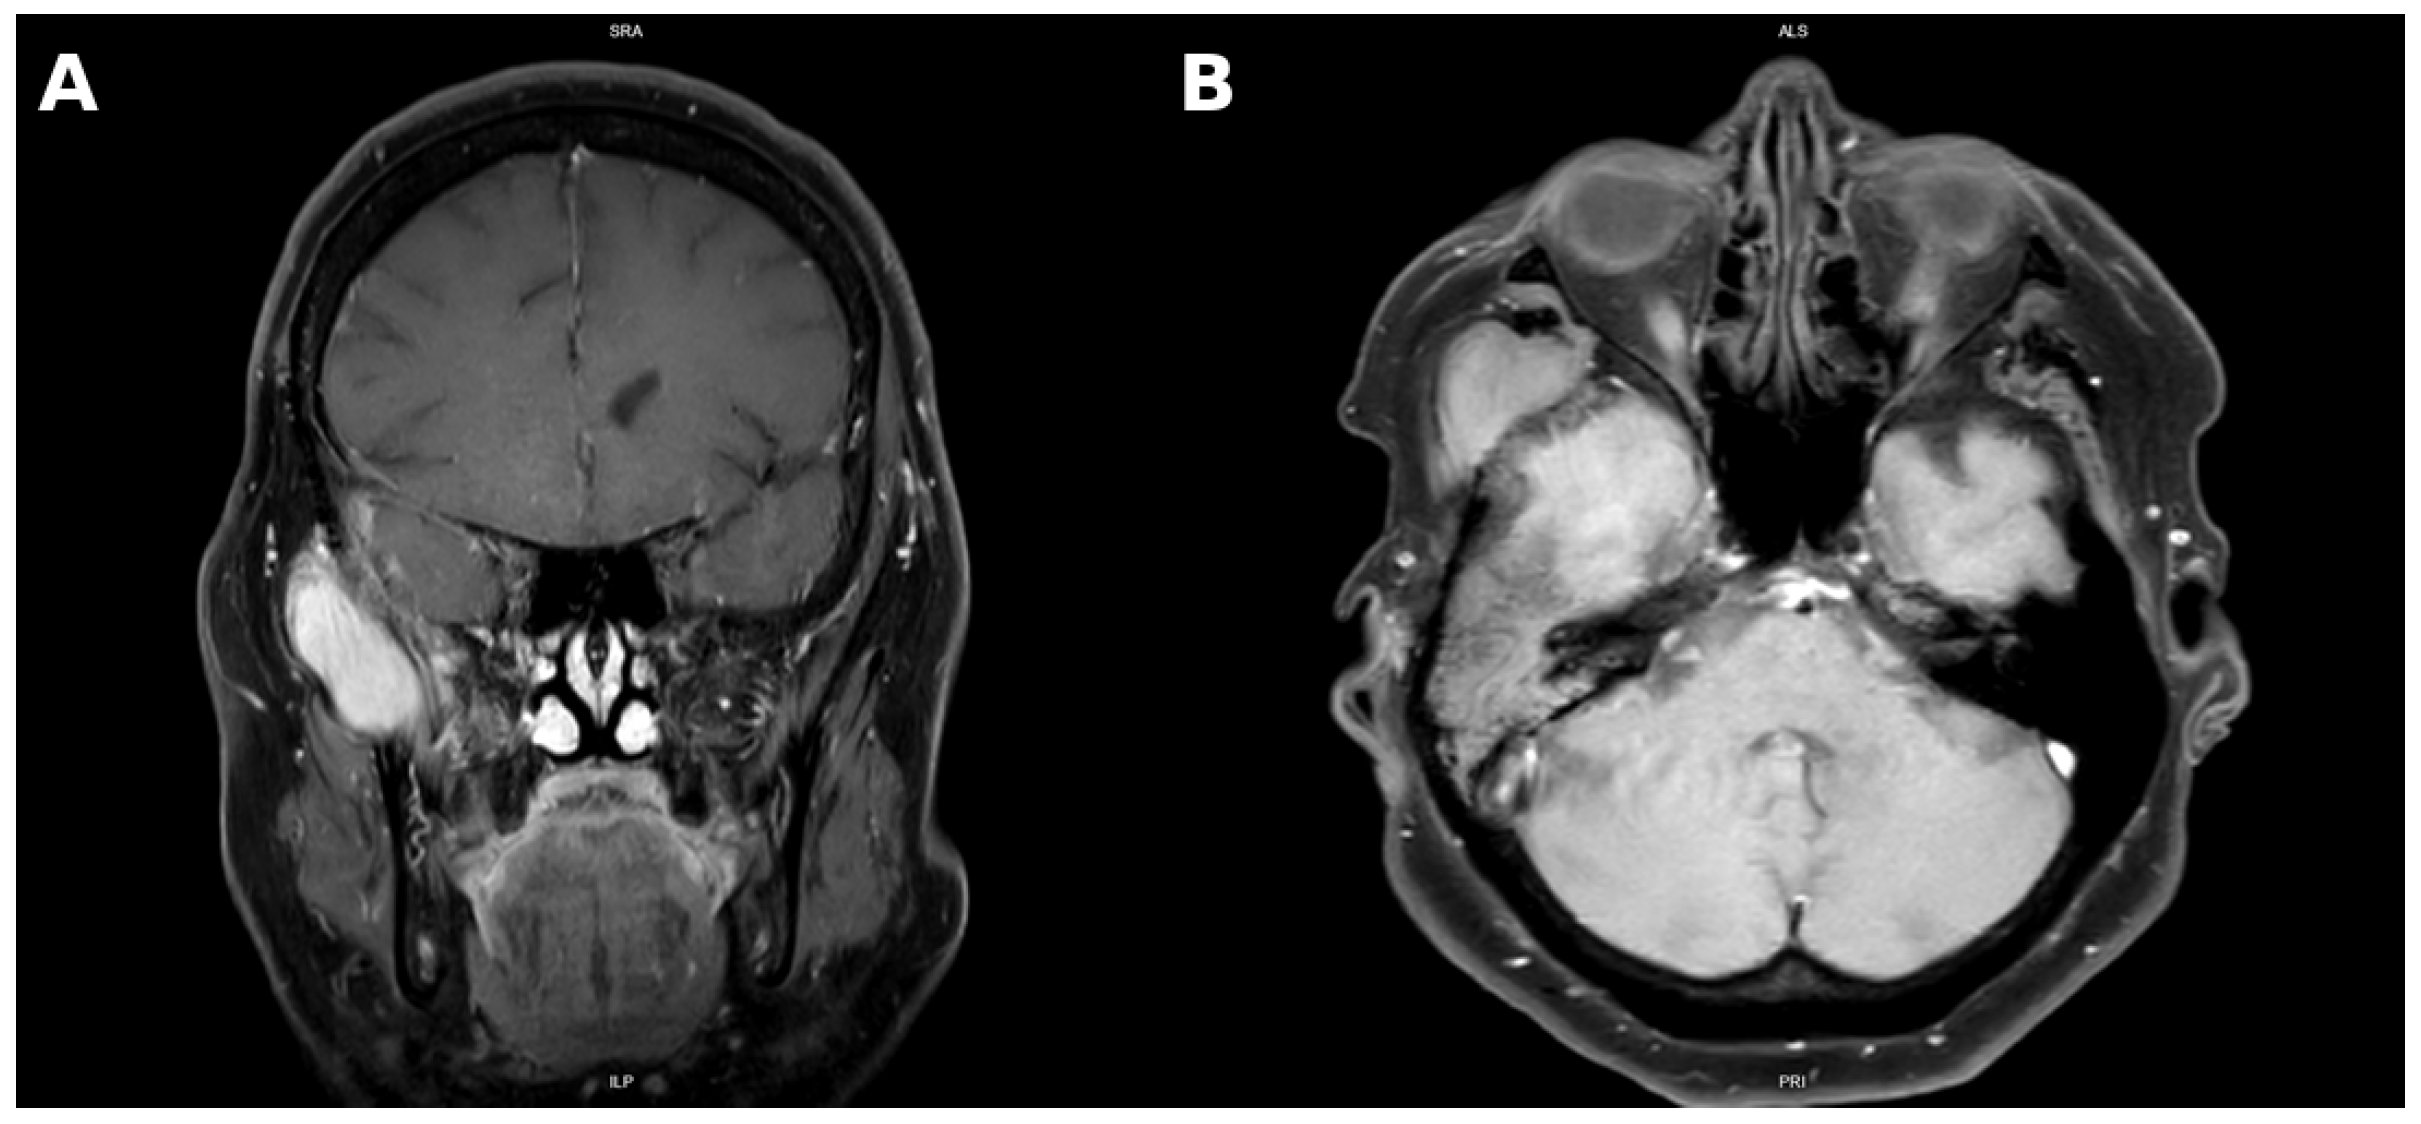

3. Case Presentation